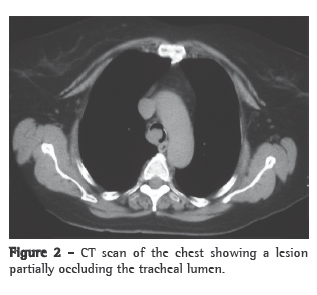

We decided to investigate concomitant conditions that might be responsible for the worsening of the clinical profile. A CT scan of the chest showed a vegetative lesion of the trachea, located 1.0 cm from the carina, resulting in significant luminal narrowing (Figure 2). Fiberoptic bronchoscopy revealed a violaceous endobronchial lesion, with well-defined borders and a smooth surface, lodged in the right wall of the trachea and obstructing 90% of the lumen. No biopsy was performed.